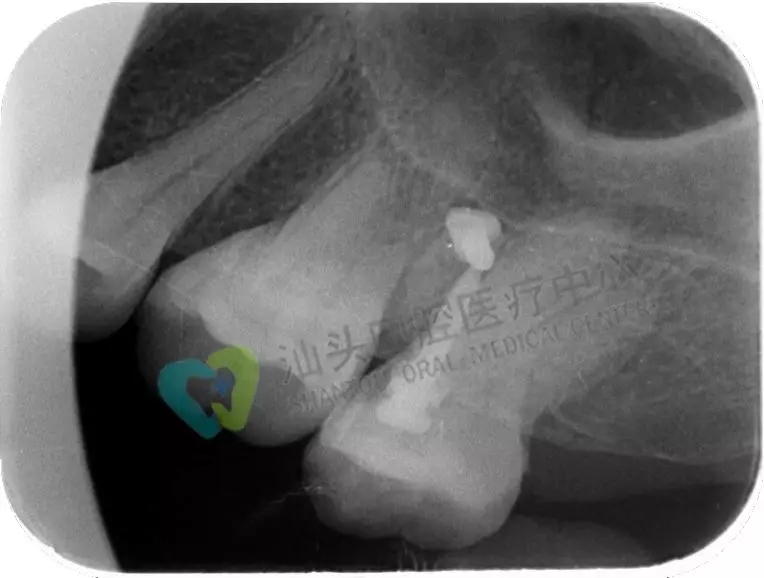

小牙片,也稱根尖片。一張牙片可以顯示3-4個(gè)牙齒,牙齒在牙片上顯示出白色阻射影像。臨床上,利用牙片對(duì)牙齒硬組織病變、牙髓病變、尖周病變及牙周病進(jìn)行診斷治療。